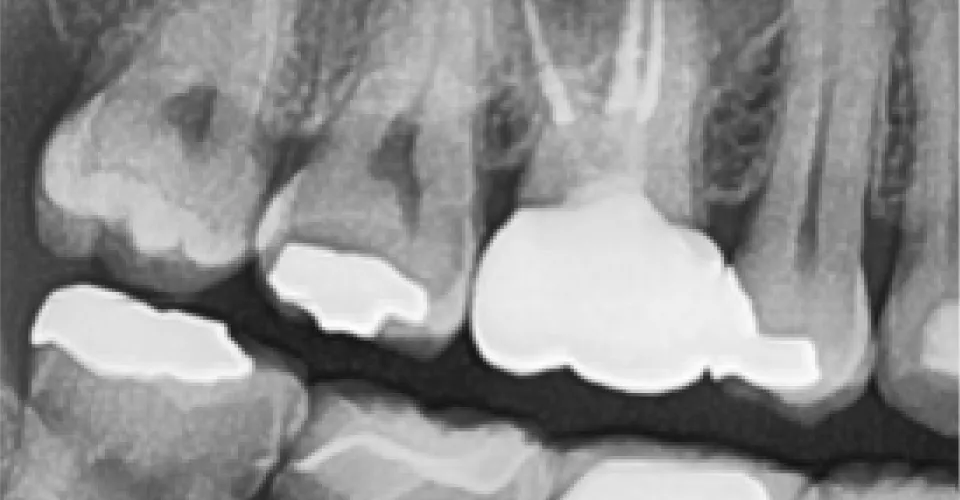

症例2

- 治療名

- 精密根管治療(大臼歯)

- 患者様

- 40代 男性

- 執刀医

- Dr. 松田

- 治療期間

- 2回

- 治療費

- 132000円

- リスク

- 術後一過性疼痛の発生